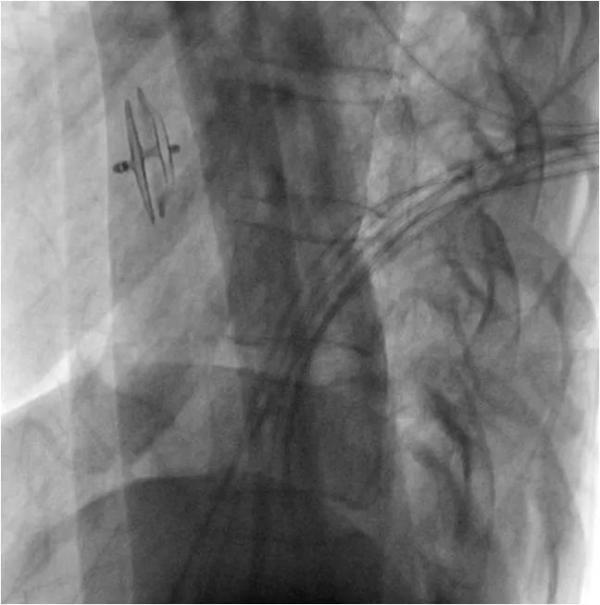

明确诊断后 , 心内科为李女士安排了手术 。 2021年1月8日 , 荆志成主任带领先心病微创手术团队 , 为患者实施了卵圆孔未闭封堵术 。 经大腿根部的股静脉微创置入心脏导管 , 将封堵器送到卵圆孔位置后 , 展开封堵伞 , 与卵圆孔完美契合 , 封堵住缺口 。 荆志成主任凭借娴熟的手术操作 , 只用了短短的5~10分钟 , 就彻底消除了一个“隐匿性杀手” , 解除了再次发生心源性卒中的隐患 。 李女士在术后第二天就恢复良好 , 顺利出院 。

卵圆孔未闭封堵术中 , 采用封堵伞堵住缺口 。